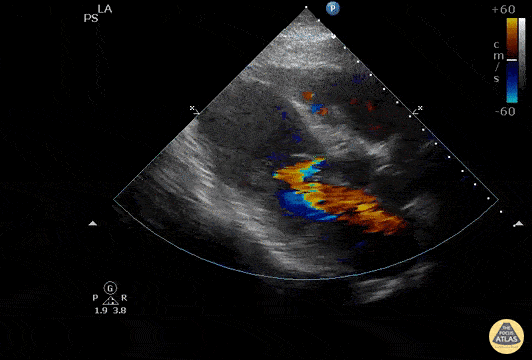

This patient presented with worsening “GERD” symptoms over the past 8 days, found to have markedly elevated troponin and anterior STEMI on ECG. The parasternal long axis view revealed a ventricular septal defect. Using color doppler, flow can be visualized as the color jet passing across the septum. Image courtesy of Robert Jones DO, FACEP @RJonesSonoEM Director, Emergency Ultrasound; MetroHealth Medical Center; Professor, Case Western Reserve Medical School, Cleveland, OH View his original post here